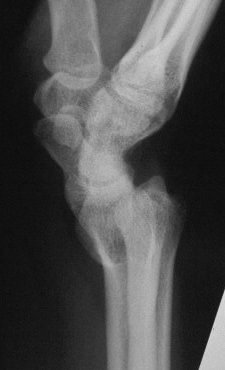

Case 3. Adult bilateral congenital Madelung's deformity with pain and extensor tendinitis, treated with the Sauve Kapandji (Lauenstein) procedure: segmental distal ulnar ostectomy and distal radioulnar joint fusion.

The right side, preop: